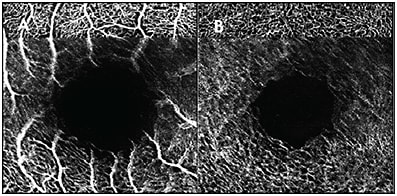

- Blink, or dry eye, artifact presents as gradual blurring and loss of signal in the direction that the scans are captured (Figure 1). This can be remedied by applying artificial tears before imaging.

Figure 1. Blink artifact shown on the OCTA superficial vascular complex (A) and deep vascular complex (B). Note the sudden transition from the sharp vasculature toward the top of the images, then the gradual reconstitution of the sharpness toward the bottom.  - Motion artifacts present as sudden, abrupt disruptions in the image (Figure 2). These occur when the patient suddenly moves their eyes. On review of the OCT B-scans, some of the images may be inverted due to patient movement.